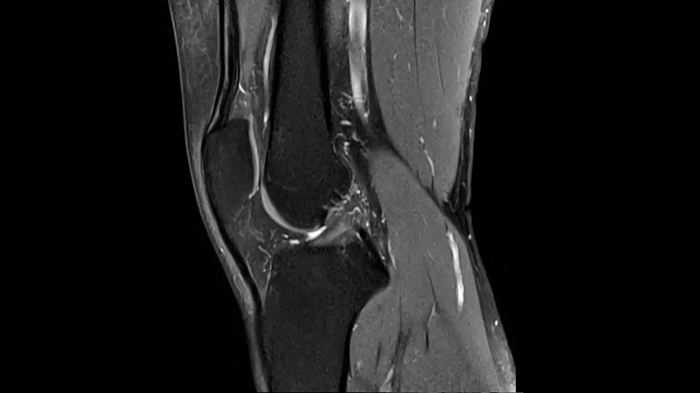

Knee

PD TSE Fat Sat with Deep Resolve and Simultaneous Multi-Slice

For clear imaging of the knee, outstanding fat suppression and performance are possible. Integrating the influence of Deep Resolve with the established Simultaneous Multi-Slice technique.

SMS 2 | Deep Resolve Gain & Sharp

0.4 x 0.4 x 3.0 mm2

TA 2:56 minutes

MAC-ID: 7aaaa0198. Image Credit: Siemens Healthineers